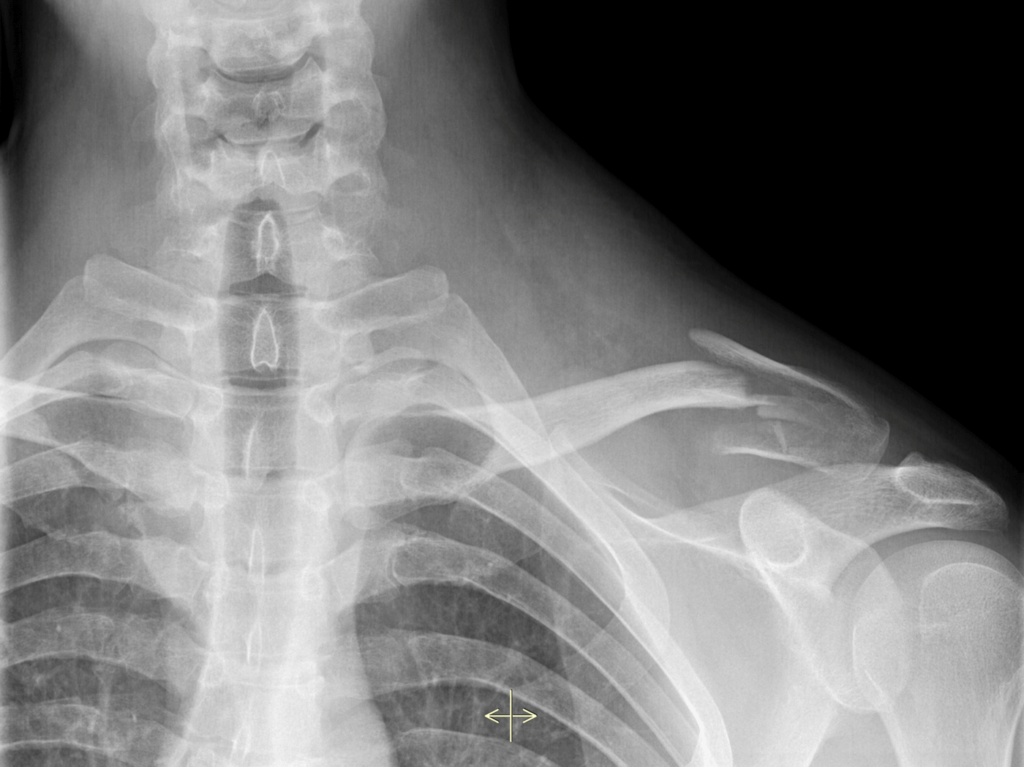

Traumatic injuries require prompt, precise care. At Ellis & Badenhausen Orthopaedics, our physicians provide expert evaluation and treatment for fractures, dislocations, and complex musculoskeletal injuries.

Orthopedic trauma care goes beyond simply setting a bone. Our surgeons carefully assess the severity of each injury, surrounding soft tissue damage, joint involvement, and overall patient health before developing a personalized treatment plan.

Treatment may include non-surgical management such as bracing or casting, or advanced surgical techniques when stabilization is required.

When surgery is necessary, our team utilizes modern orthopedic trauma techniques designed to restore alignment and stability while minimizing complications. Depending on the injury, treatment may involve: